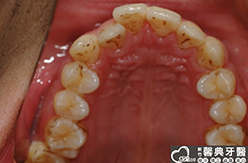

上、下顎前突,俗稱暴牙,由於上下前牙向前暴出,在外觀上容易產生牙齒外露的現象,雙唇較難自然閉合,嘴唇看也來也會比較厚。

患者︰趙同學,20多歲,學生。

主訴︰齒列不正,暴牙,不好看。

治療計劃︰上下顎齒列平整、後縮,重建正常咬合關係。